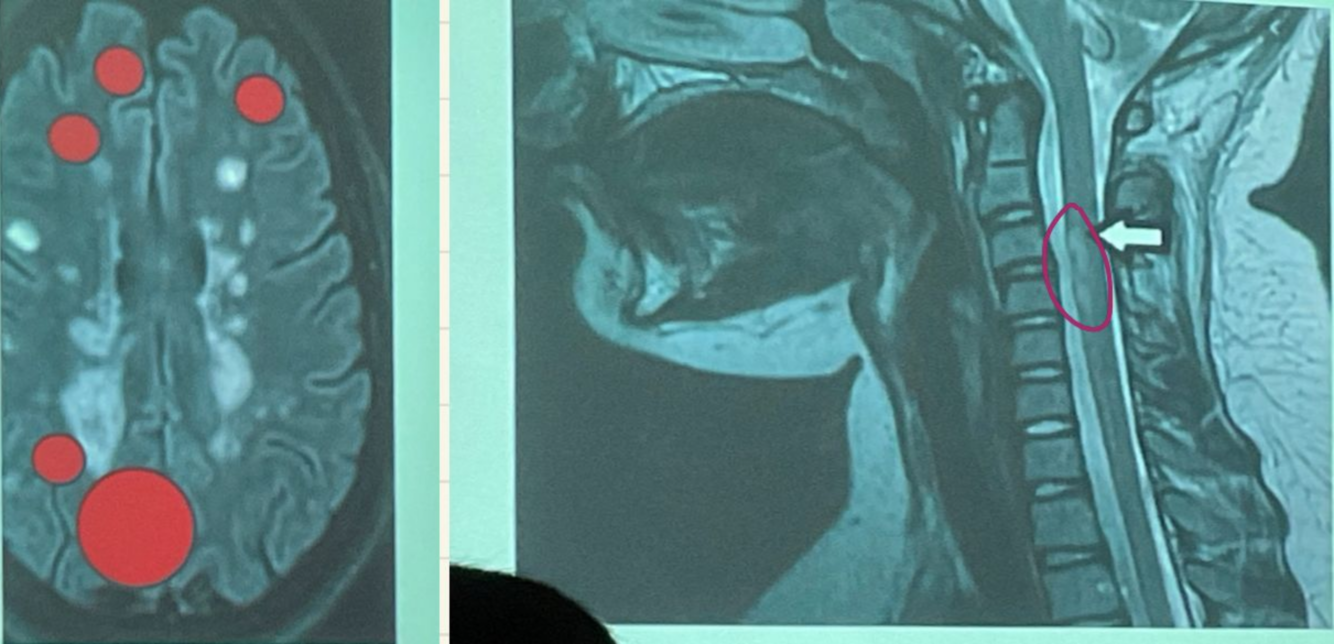

Esta resonancia corresponde a ADEM/EM

EM

ADEM

En la resonancia magnetica la esclerosis multiple da estos signos:

Hiperintensidad en T2 y FLAIR

Hipointensidad en T1

Lesiones redondas y ovaladas, bordes definidos menores a 5mm